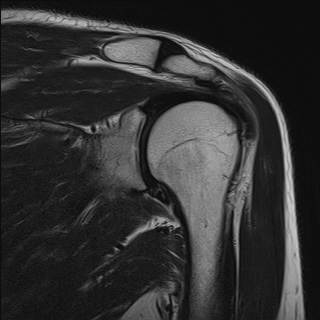

±Ø»ó°Ç³»Ãø Á¾´Ü¸é°Ë»ç¿¡¼­ ±Ø»ê°Ç ºÎÂøºÎÀÇ  ÀÛÀº ÆÄ¿­°ú Á¡¾×³¶ ºÎÁ¾ÀÌ °üÂûµÊ(±×¸² 2, 3).

±Ø»ó°Ç ¿ÜÃø Á¾´Ü¸é°Ë»ç ½Ã Á¡¾×³¶ ºÎÁ¾ÀÌ °üÂûµÊ(±×¸² 4).

±Ø»ó°Ç ±ÙÀ§ºÎ ±Ø»ó°Ç ³»ÃøÀÇ Àú¿¡ÄÚ ºÎÁ¾°ú Á¡¾×³¶ ºÎÁ¾ÀÌ °üÂûµÊ(±×¸² 5).

±Ø»ó°Ç ¿øÀ§ºÎ ±Ø»ó°Ç ºÎÂøºÎ ÀÛÀº ÆÄ¿­ÀÌ °üÂûµÊ(±×¸² 6).

ÀÚ±â°ø¸í°Ë»ç

±Ø»ó°Ç ÆÄ¿­, Á¡¾×³¶¿°, °ßºÀÇÏ °ñ±Ø